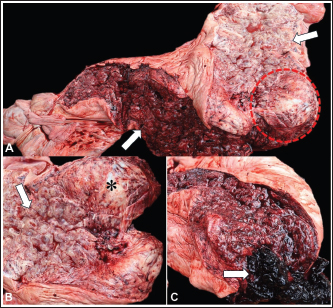

At necropsy, the elephant was in good body condition, with moderately pale mucous membranes. The uterus was markedly enlarged, and projecting from the uterine wall into the lumen of the right uterine segment, there was a poorly defined, white, firm nodule measuring 10 × 10 × 8 cm in diameter. In addition, multiple cystic dilations ranging from 0.5 to 4 cm in diameter were observed throughout the uterine segment (Fig. 1A–C). The mucosa was diffusely red with a moderate amount of crumbly clots in the lumen (Fig. 1C).

Fig. 1. Macroscopic findings of uterine leiomyoma and cystic endometrial hyperplasia in an Asian elephant (Elephas maximus). A) Uterus: markedly enlarged; projecting from the uterine wall into the lumen of the right uterine segment, white nodule measuring 10 × 10 × 8 cm (dashed); multiple cystic dilations with a thin wall, ranging from 0.5 to 4 cm (arrow), and diffusely red mucosa. B) Right uterine segment: showing the nodule (*) and cystic dilations in the mucosa (arrow). C) Left uterine segment: showing cystic dilatations and red mucosa; moderate amount of crumbly clot in the lumen.